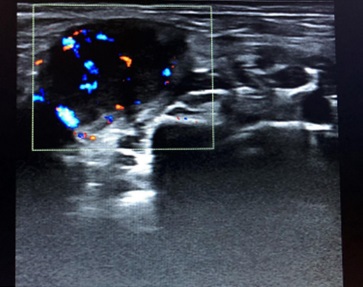

Niño de 7 años que tras vacunación de SARS-CoV-2 presenta bultoma axilar derecho generando asimetría a nivel pectoral. Asintomático. En la exploración física: adenopatía de consistencia elástica, móvil y dolorosa a la palpación. Se realiza ecografía objetivando una adenopatía hipoecoica, ovalada de 15 mm de diámetro anteroposterior, bordes hiperecogénicos bien delimitados e hilio llamativamente grande (Fig. 1) con vascularización central (Fig. 2). Diagnóstico de adenopatía reactiva, con seguimiento ecográfico al mes (Fig. 3) y disminución del tamaño.

Figura 3. Control al mes de misma adenopatía

Figura 3. Adenopatía reactivas